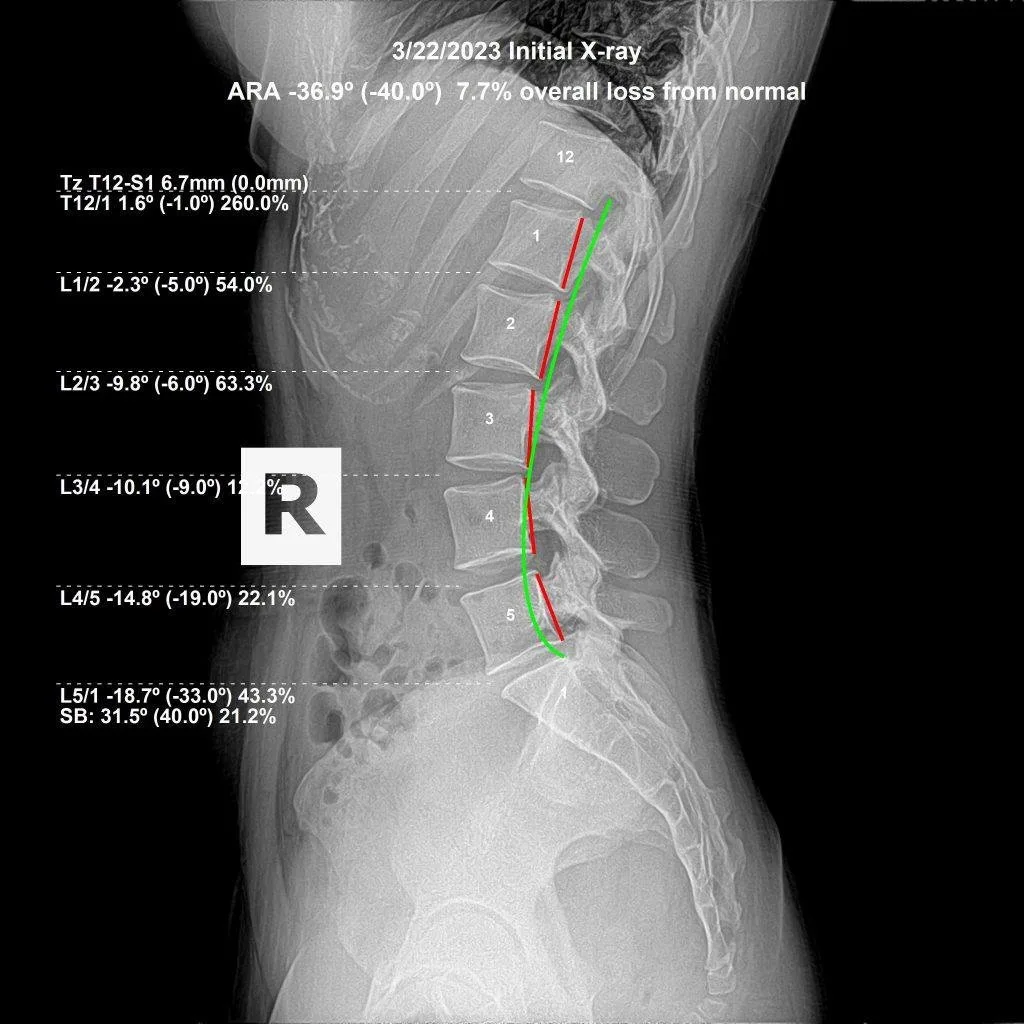

Initial lumbar X-ray showing spinal subluxation — 7.7% loss from normal curve

Initial X-ray · 7.7% loss from normal

Actual patient X-rays — lumbar subluxation correction tracked with before and after imaging at Rochet Family Chiropractic.

Subluxation-based correction works differently. The goal is to restore the vertebra to its correct structural position — measured by before and after X-rays — so that the nerve irritation, muscle guarding, and disc stress are removed at their source. When the structure is corrected and maintained, the body no longer has the mechanical reason to produce that recurring pain response.

It depends on how long the subluxation has been present and the degree of structural distortion. Recent subluxations correct faster than patterns that have been present for years. Most patients notice functional improvement within weeks; measurable structural correction — confirmed by progress X-rays — typically develops over months of consistent care. Dr. Rochet will give you a specific timeline based on your initial X-ray findings.